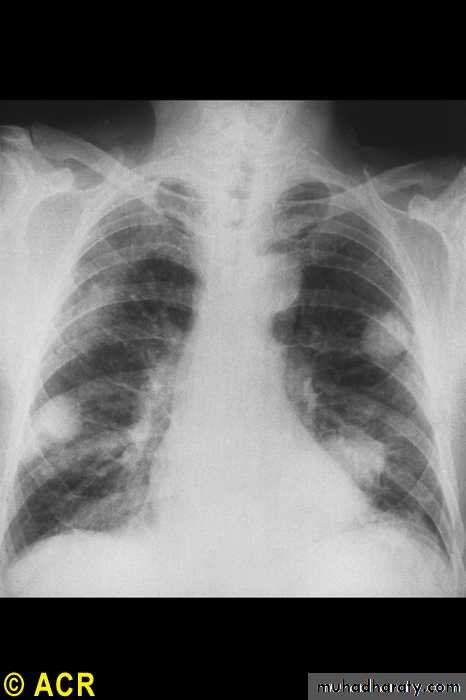

Pulmonary

Nodules

Pleural effusions

Fibrosing alveolitis

Bronchiolitis

Caplan's syndrome

Rheumatoid arthritis: pulmonary nodules

Rheumatoid Arthritis

40